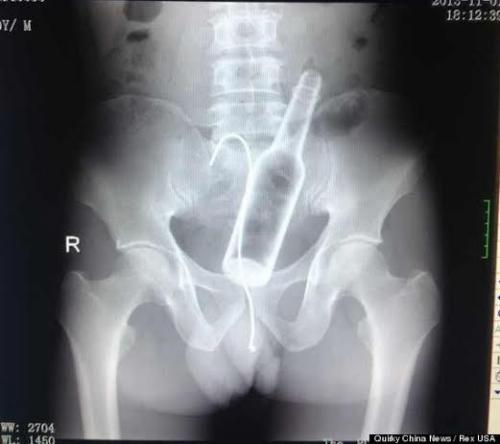

أجرى أطباء صينيون أشعة سينية لمريض كان يشكو من آلام مبرحة في بطنه، ليكتشفوا وجود زجاجة راكدة بها، وهو ما لم يجدوا له تفسيراً لدى المريض نفسه!وبعد أن أطلع الأطباء المريض، الذي لم يرغب في الكشف عن هويته، على صور الأشعة، أدلى بملابسات وصولها إلى أمعائه، بعد أن جلس عليها عن طريق الخطأ،

موضحاً أنه حاول استخراجها بسلك عن طريق الفم لكنه لم ينجح، وخاصة بعد أن سقط السلك في بطنه أيضاً مما دفعه إلى زيارة طبيب.وخضع المريض إلى جراحة لاستخراج السلك والزجاجة، التي تسببت له في بعض الجروح الداخلية بالأمعاء، حسبما ذكرت صحيفة “ميرور” البريطانية.